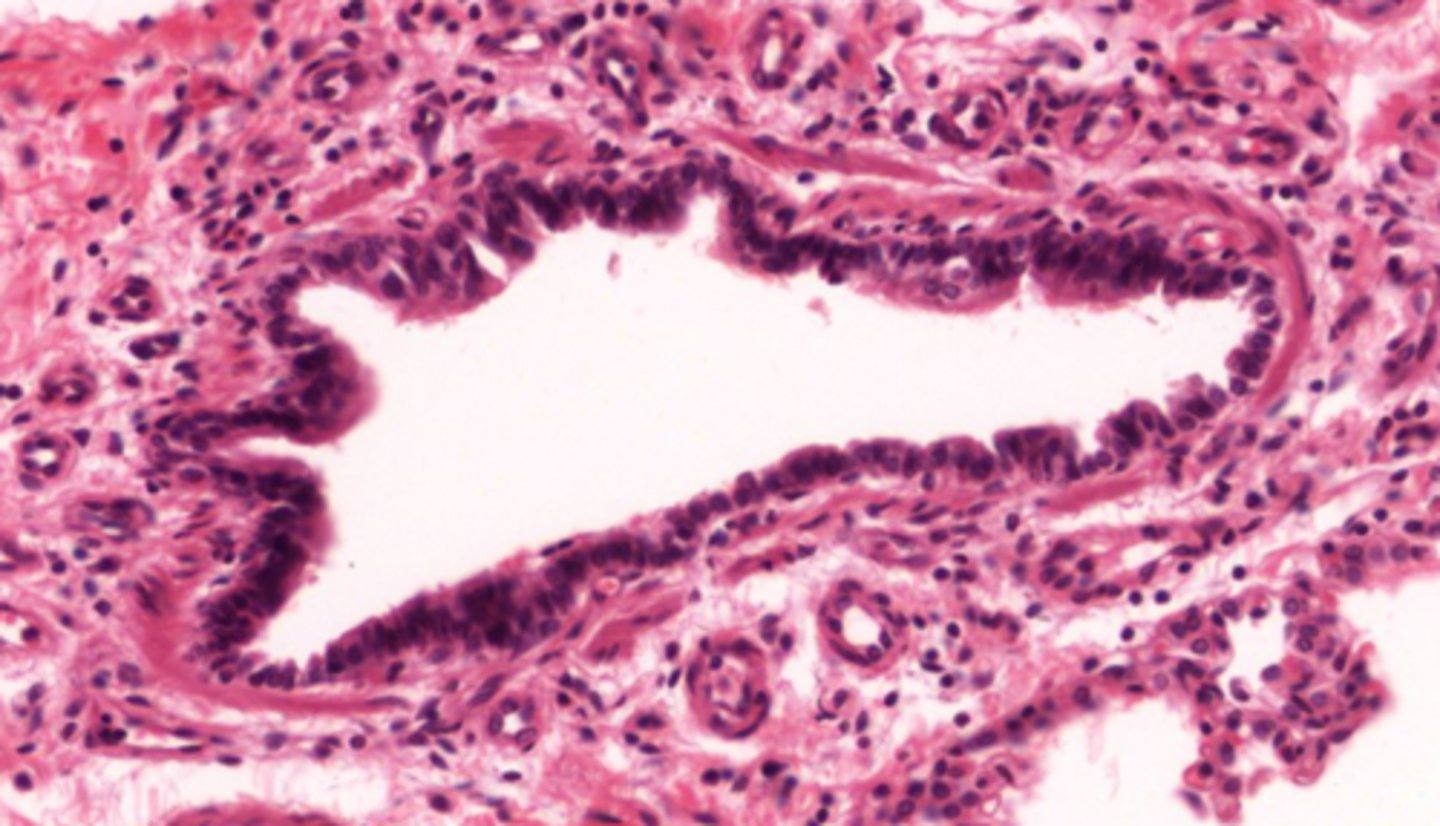

Identify the type of bronchiole

terminal bronchioles

respiratory bronchioles